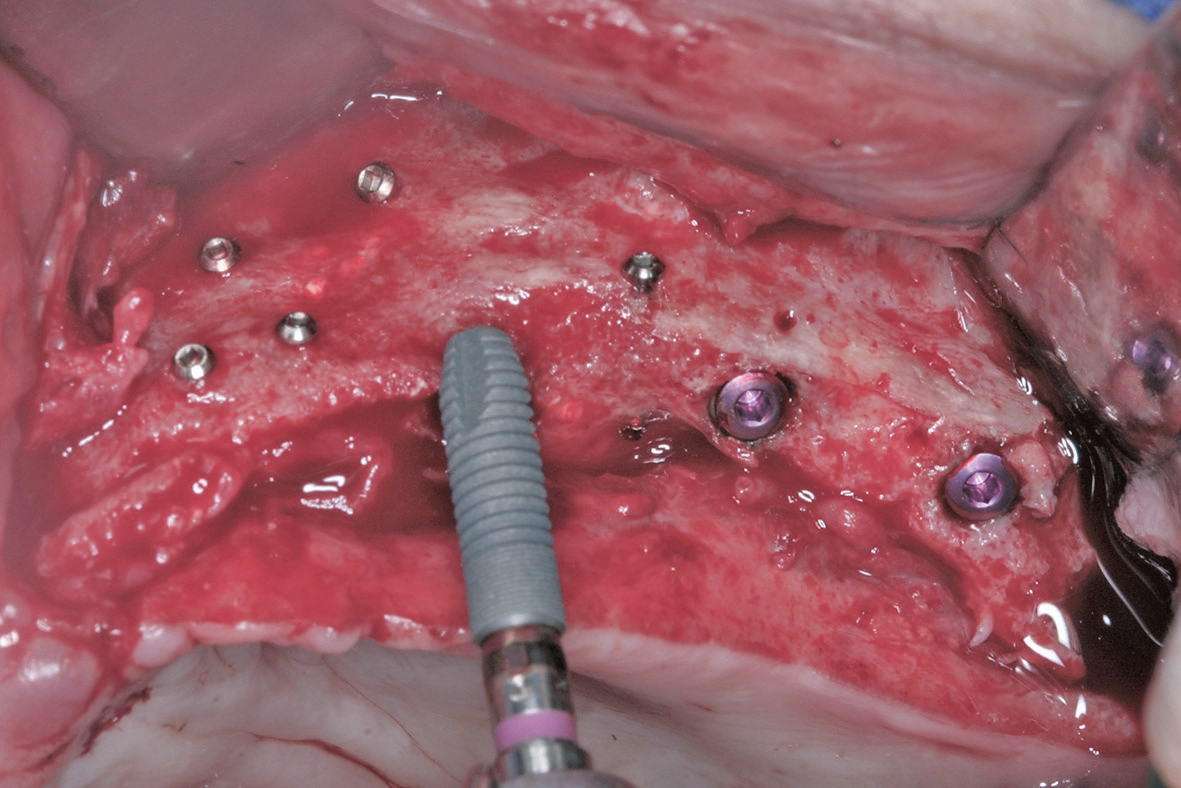

Der chirurgische Behandlungsteil bestand aus drei Eingriffen im Abstand von jeweils drei bis vier Monaten. Im ersten Eingriff wurden die augmentativen Maßnahmen im atrophierten Oberkiefer nach retromolarer Knochenentnahme aus dem rechten Unterkiefer in horizontaler und vertikaler Dimension vorgenommen (Abb. 4). Dazu wurde der Empfängerkiefer durch das Anbringen von autologen Knochenblöcken nach dem biologischen Konzept lateral verbreitert. Mittels der Schalentechnik wurden dabei die Blöcke auf Distanz gesetzt und der Zwischenraum mit autologen Knochenpartikeln gefüllt (Abb. 5a u. b). Durch die Partikulierung des Knochens wird die Oberfläche vergrößert und es kann eine bessere Revaskularisierung des augmentierten Bereichs erfolgen [5].

Vor dem zweiten OP-Eingriff nach 4 Monaten wurde im Labor eine Bohrschablone hergestellt. Zudem wurde ein DVT angefertigt, um im Sinne eines backward planning die idealen Implantatpositionen zu ermitteln. Bei Eröffnung des augmentierten Kieferbereiches zeigte sich eine gute Regeneration und Revaskularisierung des Knochens. Sechs Implantate konnten mit ausreichender Länge und passendem Durchmesser so in den augmentierten Bereich (Astratech EV®, Dentsply Sirona Implants, Mannheim) inseriert werden, dass sich eine gleichmäßige Pfeilerverteilung ergab (Abb. 7 u. 8).